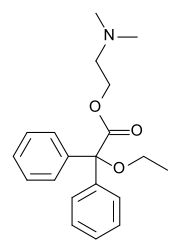

Phenalkoxams

- Dextropropoxyphene (propoxyphene)

- Dimenoxadol

- Dioxaphetyl butyrate

- Levopropoxyphene

- Norpropoxyphene

- Pyrroliphene

Structures

| Phenalkoxams | ||||

|---|---|---|---|---|

Dextropropoxyphene |

|

|

|

|